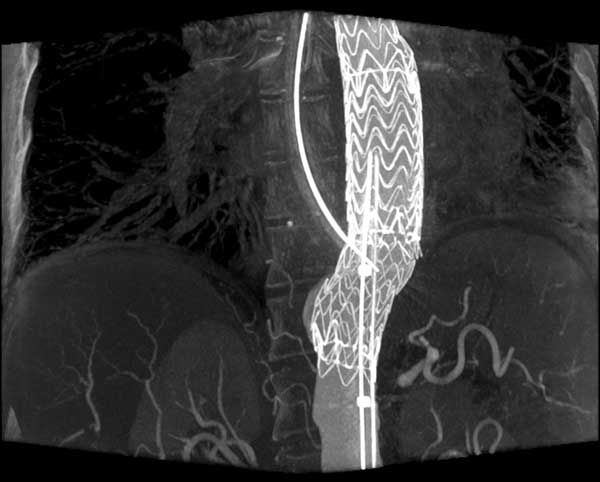

![]() |

| Figure 2. Aortic stent graft visualized with 3D CT-like imaging. Courtesy of Deutsches Herzzentrum Berlin, Germany Courtesy of Prof. Fosse, Rikshospitalet, Oslo, Norway. |

Endovascular aortic repair

Endovascular repair (EVAR) for the abdominal aorta in chronic aneurysms has become a valid alternative to open repair with superior survival (17). EVAR is also increasingly used for the thoracic aorta (Figure 2). In selected cases EVAR in combination with open surgery is even applied for pathologies of the aortic arch and distal ascending aorta (23).

CT-like 3D imaging with the angiography system

Surgery very much depends on 3D visualization of the anatomy and therefore 3D CT-like imaging with the angiography system is an important feature, because it enables the surgeon to navigate in real time in 3D volumes. In principle, CT-like imaging of the heart is performed by one or two sweeps of up to 220° of the C-arm around the patient. During the rotation several hundred images are acquired and then reconstructed as a 3D volume. If the acquisition is gated by an ECG 3D volumes over time can be generated to depict the beating heart. Radiation dose is comparable to a conventional multi-slice CT. The OR staff can move out of the OR completely during a CT-like run, because it lasts only approximately 10 sec. Reconstruction is performed within one minute. Accurate information of the cardiac anatomy in the operating room supports planning of complex procedures like redo operations, surgery for complex congenital heart disease, transcatheter valve replacement. Segmentation of anatomical structures and overlay of the 3D volumes over live fluoroscopy (3D roadmap) enables the surgeon to virtually navigate in 3D anatomy (Figure 2). First investigations demonstrate the value of this new technology in transcatheter aortic valve replacement (13) (Figure 6), particularly with anatomical adjustable valve prosthesis as the Ventor Embracer valves. In pulmonary valve replacement the 3D valve anatomy in relation to the coronary artery anatomy is of great importance to avoid obstruction. In EVAR (5) endoleaks can be evaluated in the operating room and corrected, if deemed necessary.